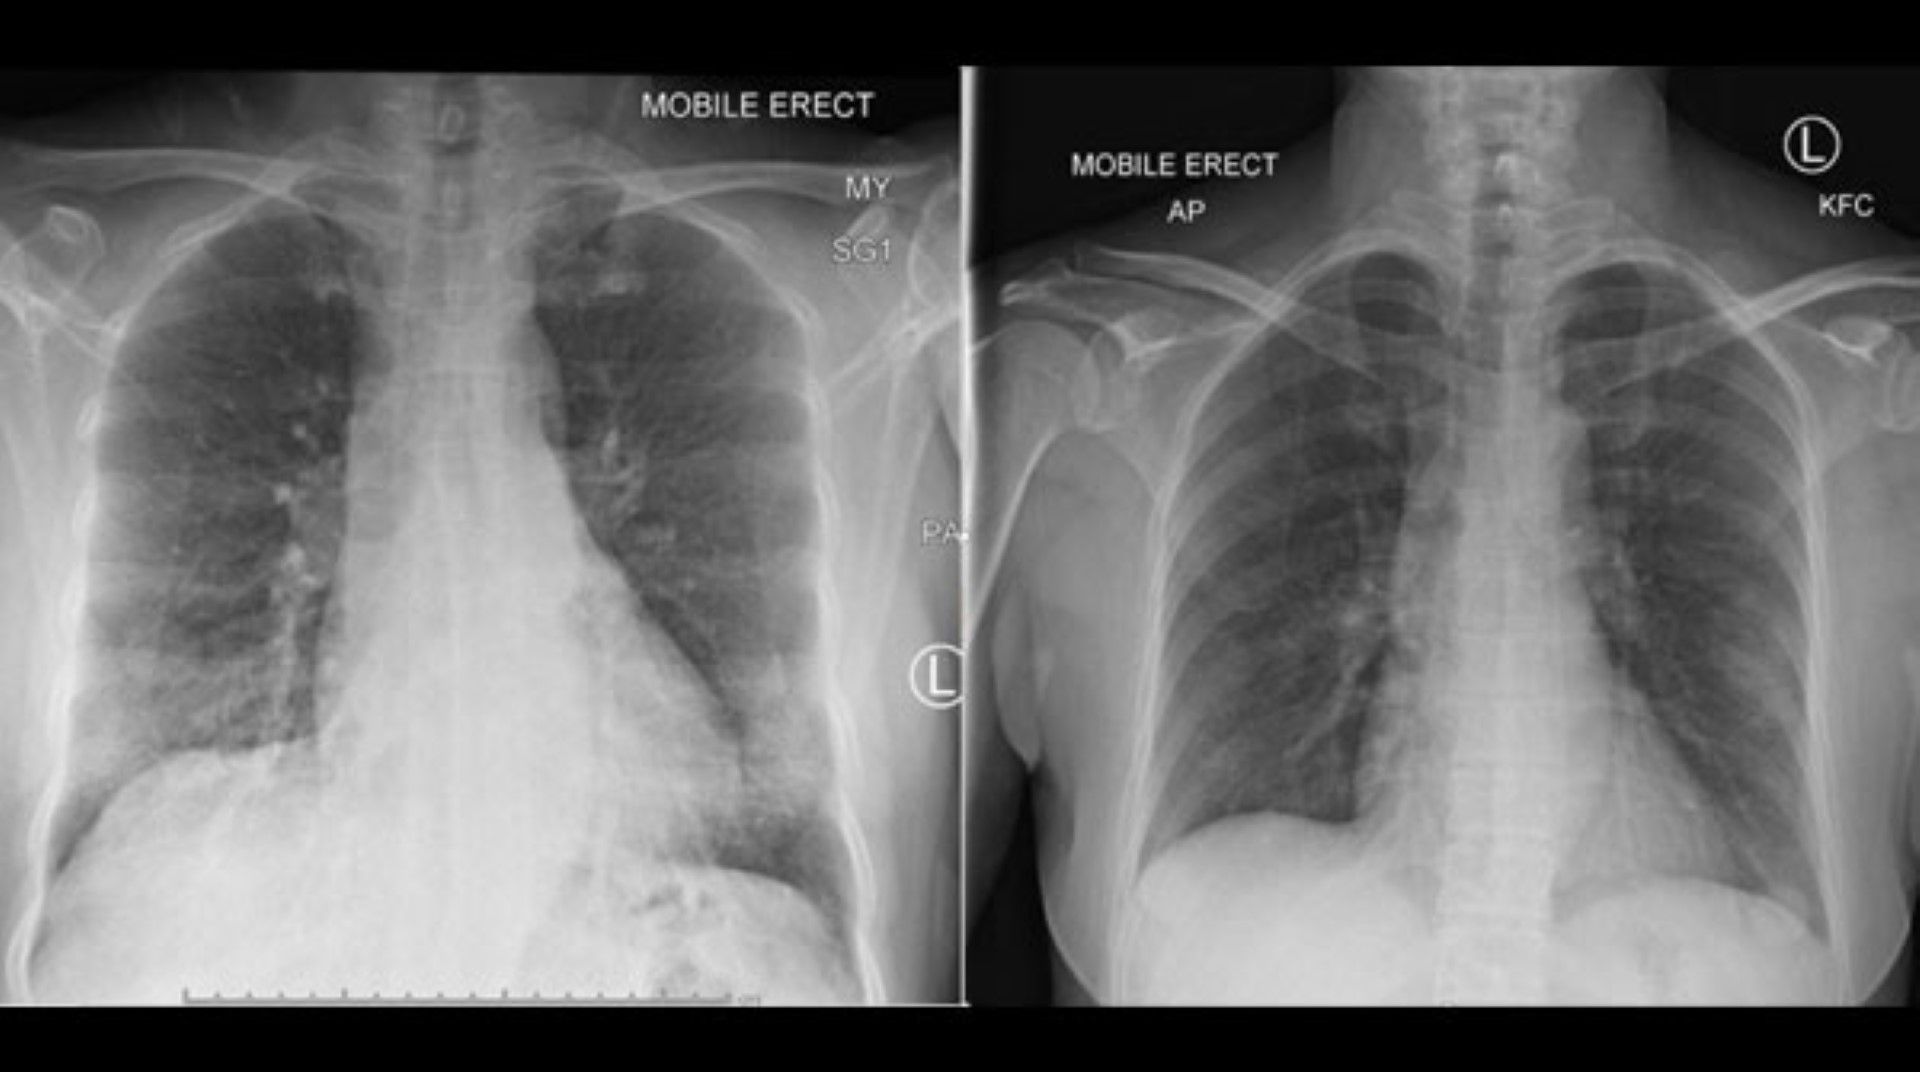

Foto/Imagem: Instituto Peter DohertyO vídeo de um hospital norte-americano mostra os pulmões de um homem que não apresentava sintomas para o novo coronavírus e, hoje, está infectado e seus órgãos estão deixando de funcionar como deveriam. A informação é de Keith Mortman, chefe do setor de cirurgia torácica do Hospital da Universidade George Washington.

A instituição divulgou, recentemente, o vídeo que mostra, em 3D, os pulmões de um paciente com Covid-19. As imagens indicam os danos extensivos causados aos órgãos de um homem de 59 anos, com pressão alta.

Nas imagens, as áreas marcadas em amarelo representam as partes infectadas e inflamadas dos pulmões, detalhou Mortman. Quando eles se deparam com uma infecção viral, começam a selar o vírus.

Nota-se que os danos não ficam restritos a apenas uma região do órgão, mas se estendem por faixas enormes dos dois pulmões, mostrando o quão rápida e agressiva a infecção pode ser, mesmo em pacientes mais novos. Uma pessoa saudável não teria as marcações em amarelo que aparecem no vídeo, segundo o médico. O paciente em questão está, agora, internado na Unidade de Terapia Intensiva (UTI), em estado grave.

Os pontos em amarelo nas imagens mostram infecções e inflamações. “Então você contrai essa grave inflamação nos pulmões como tentativa do corpo em controlar a infecção.”

As imagens sugerem que as palavras para descrever os sintomas comuns da doença – como tosse e dificuldade de respiração – não podem expressar realmente o impacto do vírus no corpo humano.